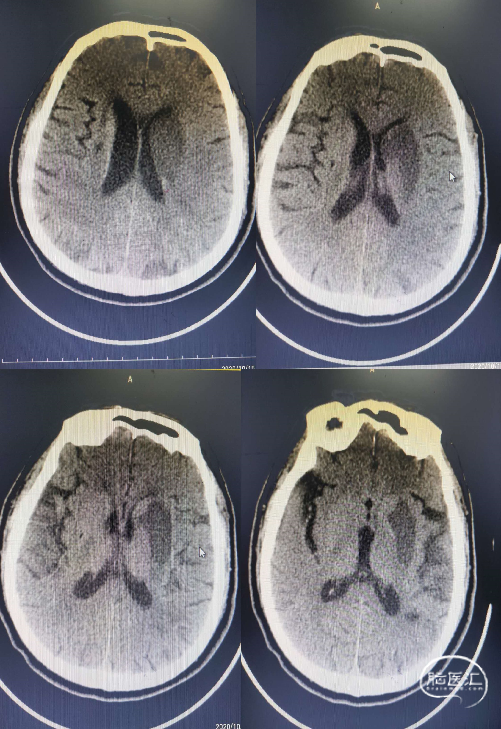

术后第二天复查CT左侧基底节区脑梗死。

术后2周神经系统查体:神志清楚,言语基本流利,双侧瞳孔等大等圆,直径3.0mm,对光反射敏感,双眼球活动自如,两侧鼻唇沟对称,右侧肢体肌力4级,左侧肢体肌力5级。

NIHSS评分:3分,mRS:1分。